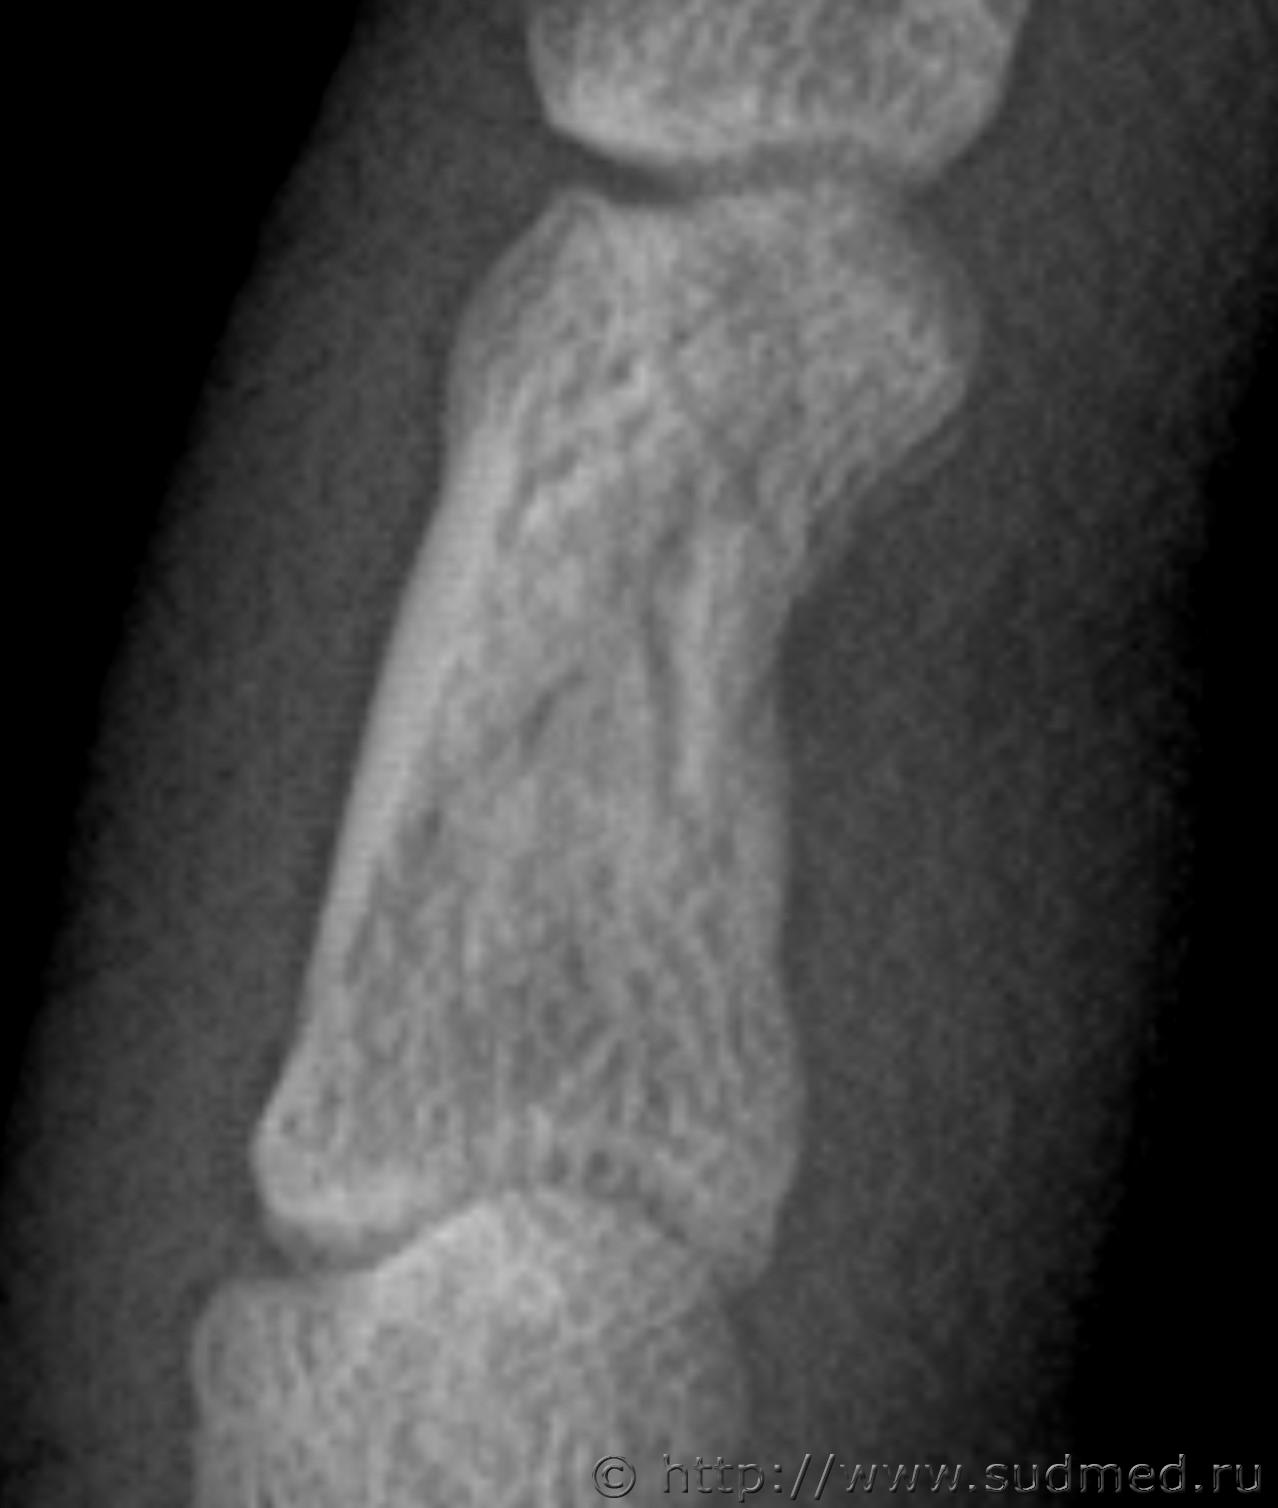

Здравствуйте. Произошла драка в которой когда я упал и меня пинали по голове, я закрыл голову рукой и нападавший попал ногой по руке. В результате он повредил мне мизинец на левой руке. Врач скорой сказала что это скорее всего ушиб. Я думал что ушиб пройдет, но палец болел и через 13 дней я обратился в травмпункт, мне сделали рентген кисти и обнаружили «З/консолидирующийся перелом о/фаланги Vп левой кисти». По этой справке мне определили средний вред здоровью. Потом когда суд мед эксперты смотрели данный снимок они не нашли перелома. Снимок сделан в травм пункте на 13 день после травмы. Можете ли вы оценить снимки. Что на них видно? Какая степень вреда здоровью?

Скорее всего технический сбой. Вот изображения в другом формате.

В справке из травм пункта на 13 день после травмы указано:

Установлен диагноз: З/консолидирущийся перелом о/фаланги Vп левой кисти.

По поводу первого снимка, 13 дней после травмы. На диске, цифровой.

Заключение: на представленных рентгенограммах 5 пальца левой кисти от (13 дней после травмы) на электронном носителе костно-травматических изменений не выявляется.

Снимки цифровые 13 дней после травмы: